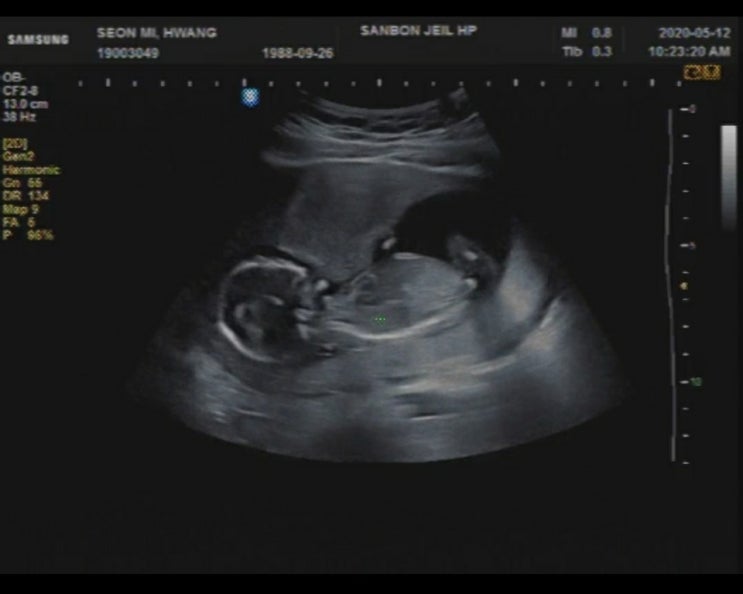

[임신18주/13.5cm] 임신5개월, 임신18주차 증상, 임신 18주 배크기, 임신 18주 태동, 임신중기, 니프트검사, 임신 18주 몸무게

이젠 누가봐도 임신한 사실을 알 수 있을 정도로 배가 눈에 띄게 불렀다. 엉덩이와 허벅지 팔뚝 옆구리 등...